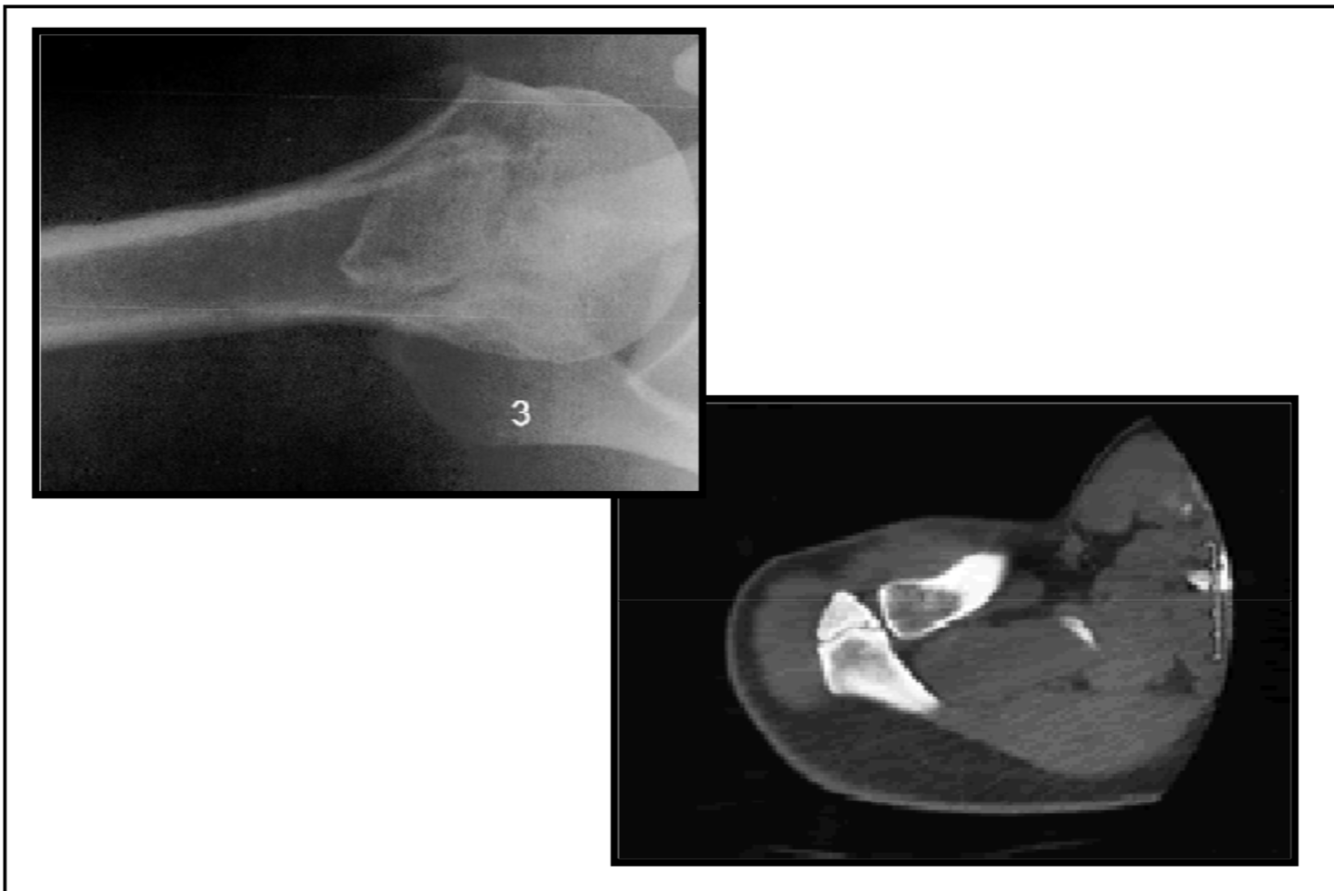

Synovial herniation pit or Pitt’s pit

variation anat normal